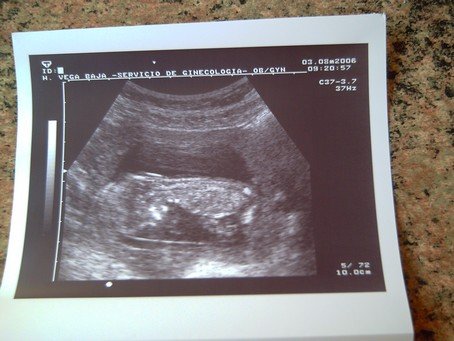

Én meg ígértem 18 hetes UH képet: :D

Az enyémen valóban látszik a koponyája, jobb oldalon,mellette látszik a pocija+még a combcsontja is bal oldalon,az alsó lábszárát eldugta valahova :D